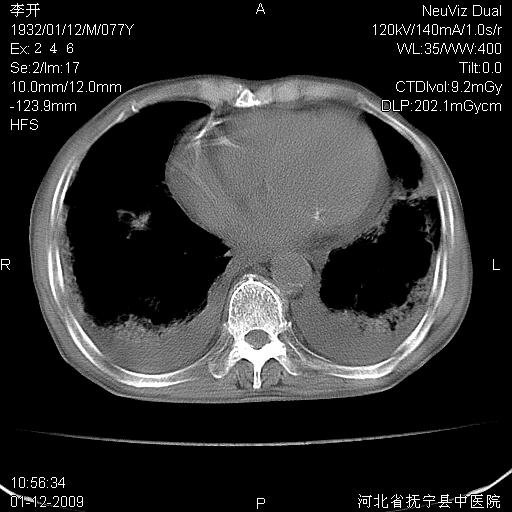

以下是引用黑白光影在2009-1-19 16:49:00的发言:[br]心衰肺水肿;心包、胸腔积液;冠脉钙化;肺部感染。